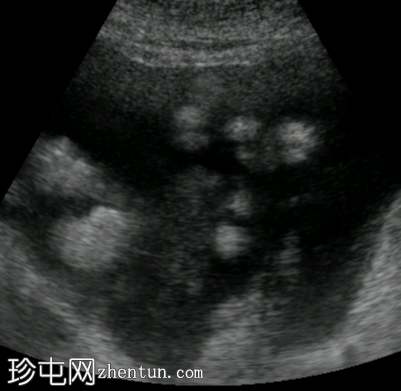

横向

超声图像显示右上腹肝脏周围存在均匀的无回声区域。左上腹脾脏附近也存在类似的无回声区域,肠管之间的盆腔内也存在无回声区域。这些积液的总体积估计为3-4升。胆囊外观未见异常,无结石或壁增厚的迹象。由于上覆肠道气体和患者体型特征,胰腺肿块未能清晰显示。

本病例显示,梗阻性黄疸患者接受胆道支架置入术后出现腹水。超声检查对检测游离液体敏感,但未能显示原发肿瘤。如果存在游离液体而无慢性肝病证据,通常需要进一步影像学检查以评估是否存在恶性肿瘤。